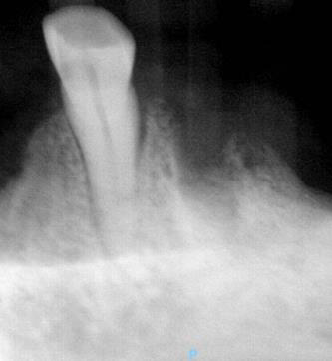

The patient is a 76-year-old female with a history of multiple myeloma who was referred by her dentist for a full mouth extraction prior to starting Zolendronic acid (Zometa) infusions. Her past medical history was further complicated by cardiovascular and pulmonary issues, along with Type II diabetes and general frailty. After discussion with her dentist, the decision was made to switch from full mouth extractions to removal of symptomatic teeth. The patient underwent removal of teeth #20, #23, #24 and #27 in August 2023 and began her infusions three months later. The patient did well and returned for removal of teeth #21 and #22 in the spring of 2025. At that time, she had also been started on a combination of daratumumab (Darzalex), a monoclonal antibody, and bortezomib (Velacade), a proteasome inhibitor, for her multiple myeloma. After two months, the patient developed pain and bone exposure at the site of #21/#22. She also reported pain in teeth #5, #14 and #16. She was diagnosed with Stage 2 MRONJ. The area was debrided and teeth #5, #14 and #16 were removed. Currently, she is pain-free and there is no evidence of bone exposure or MRONJ.